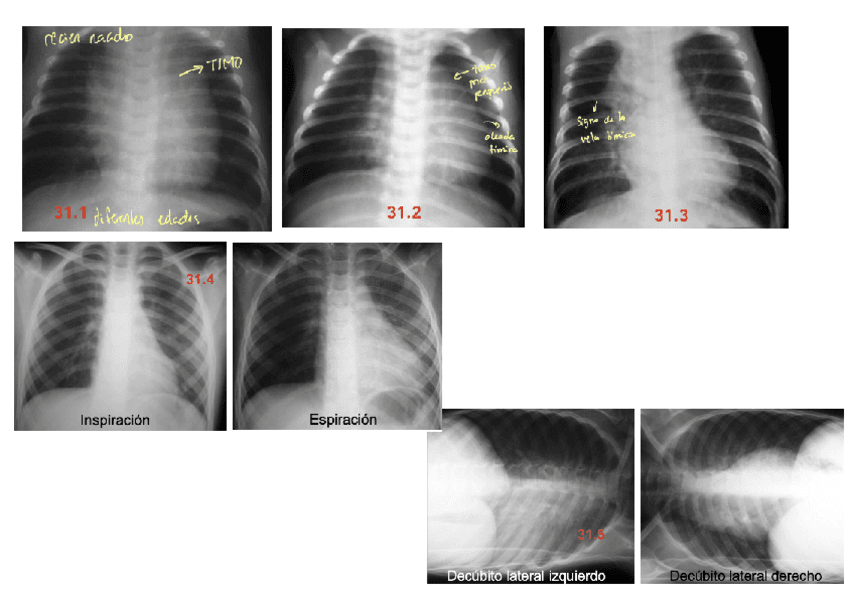

Apuntes - ANEXO-T31.pdf